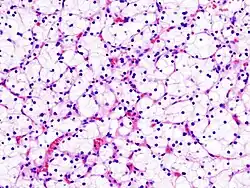

- Carcinoma renal cromófobo/oncocitoma (4 a 5% dos casos): O menos agressivo, tem crescimento lento e dificilmente se dissemina. Ao microscópio possui células grandes que não se tingem com H&E (por isso são cromófobos).